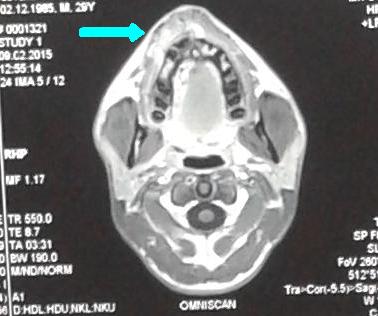

În secţia Chirurgie endovasculară s-a adresat pacientul S., bărbat de 30 ani, cu o formaţiune tumorală a feţei, cu senzaţie de pulsaţie permanentă, cu dureri periodice şi sîngerări frecvente la periaj dentar. Formaţiunea s-a dezvoltat treptat, iar în perioada pubertară a înregistrat o creştere accelerată. O serie de investigaţii (Angio-RMN şi Duplexul arterial) a stabilit diagnosticul de Malformaţie arteriovenoasă, care este o anomalie vasculară activă hemodinamic, cu flux sanguin rapid, cu afluenţi arteriali şi vene dilatate.